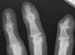

Posteroanterior (PA) radiograph of the hand reveals narrowing, osteophytes, and subchondral cysts affecting the distal interphalangeal joints; this finding is typical of osteoarthritis.

In the small joints of the hand (see the image below), radiographs often show narrowing of the entire joint. In some cases, the interphalangeal joint may be asymmetrically affected, and radial or ulnar deviation at the joint may be appreciated; volar subluxation, as seen with rheumatoid arthritis, seldom occurs.